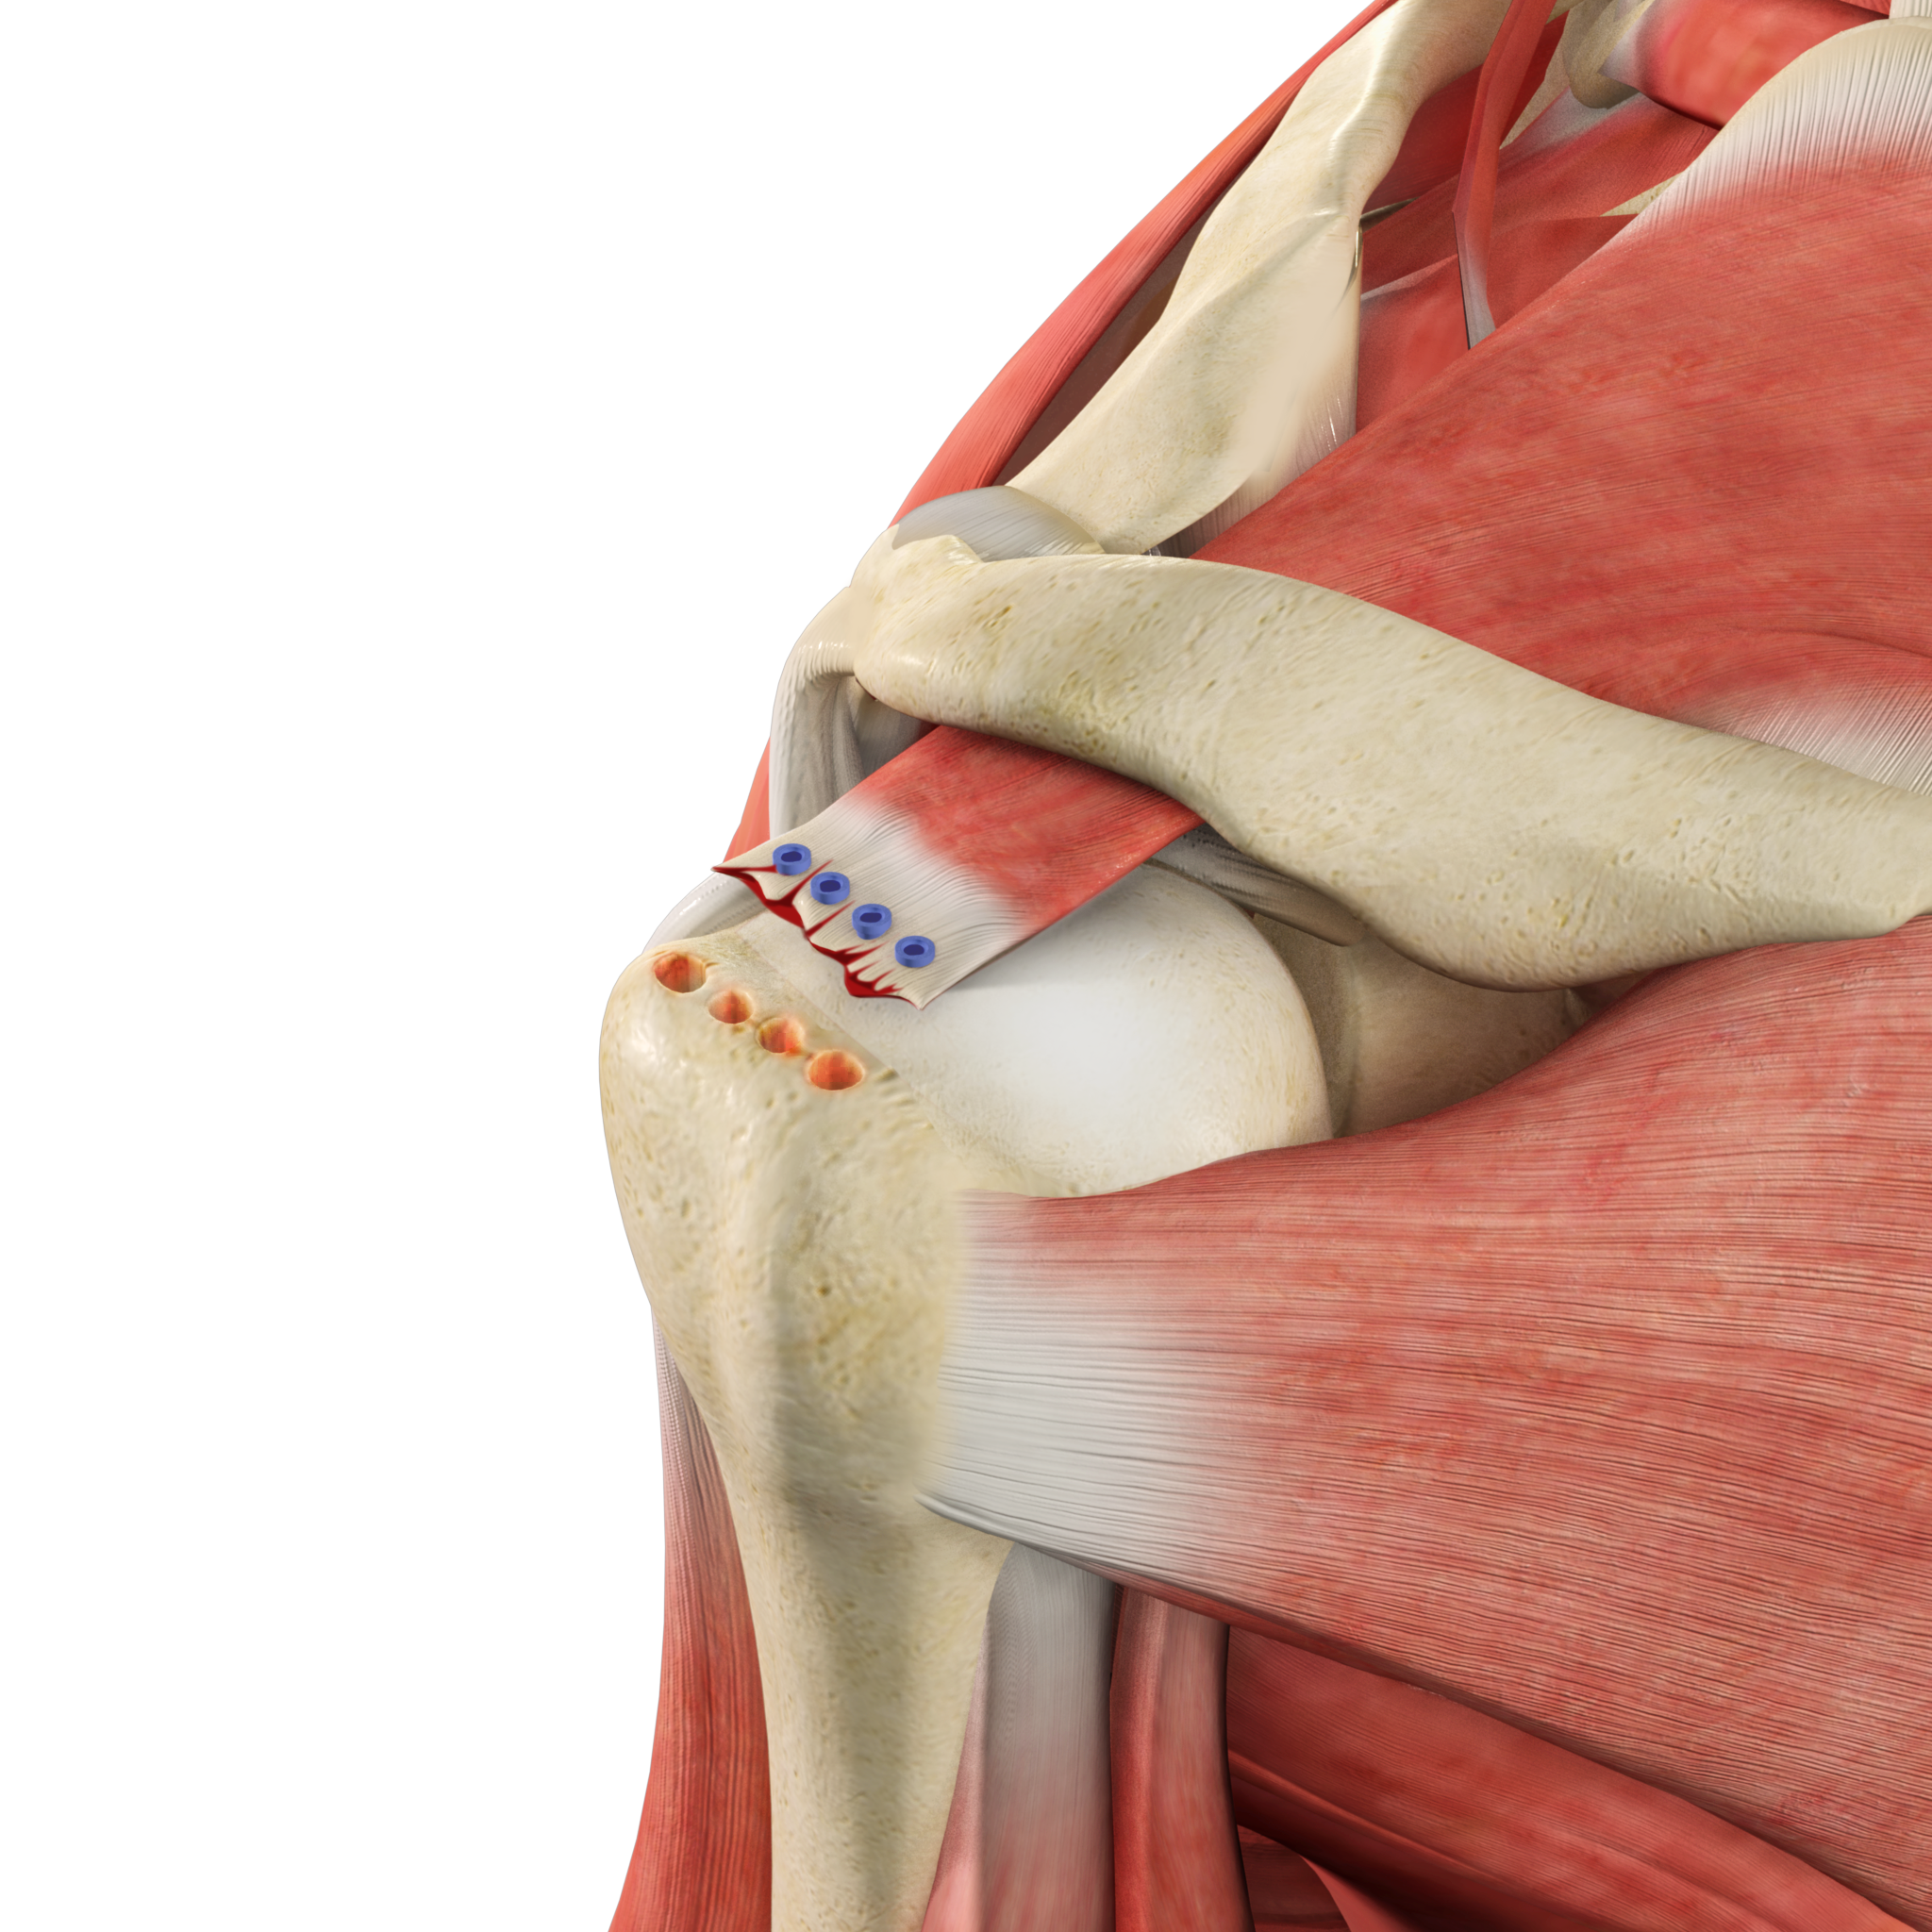

Rotator Cuff Repair

The rotator cuff is a group of 4 muscles in the shoulder joint including the supraspinatus, infraspinatus, teres minor, and subscapularis.

Revision Rotator Cuff Surgery

Revision rotator cuff surgery is a procedure done to repair a re-tear in the rotator cuff after a failed initial rotator cuff surgery.